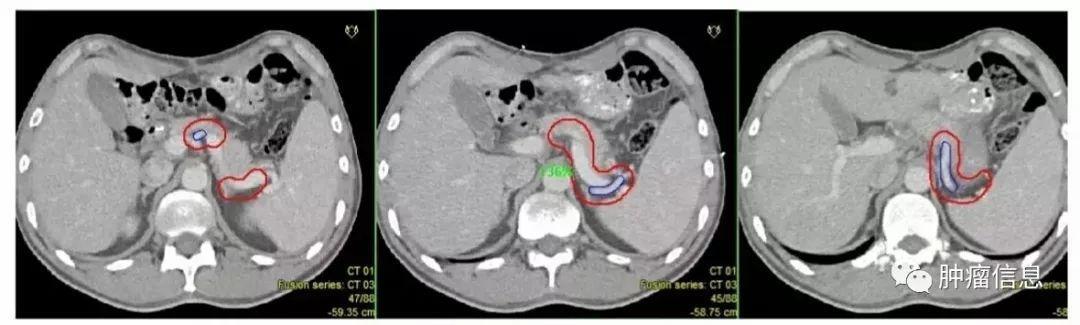

No.16腹主动脉旁淋巴结

上界:腹腔干上缘下界:L3下缘(肠系膜下动脉上缘)

No.14肠系膜根部淋巴结

分为:肠系膜上动脉组(14a)和肠系膜上静脉组(14v)

No.15结肠中动脉旁淋巴结

沿结肠中动脉分布,结肠中动脉较小,CT上很难发现,勾画时可以从受累的横结肠延伸到肠系膜根部血管区域